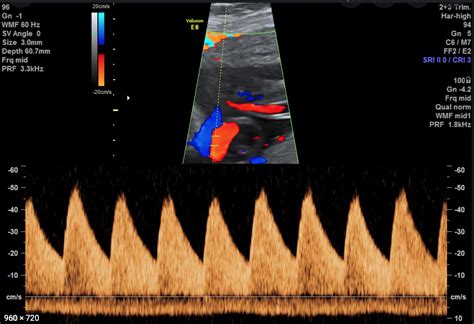

- Untersuchung von Herz und Blutfluss: Farbdoppleruntersuchung des Herzens und der Plazenta zur Beurteilung der Blutversorgung.